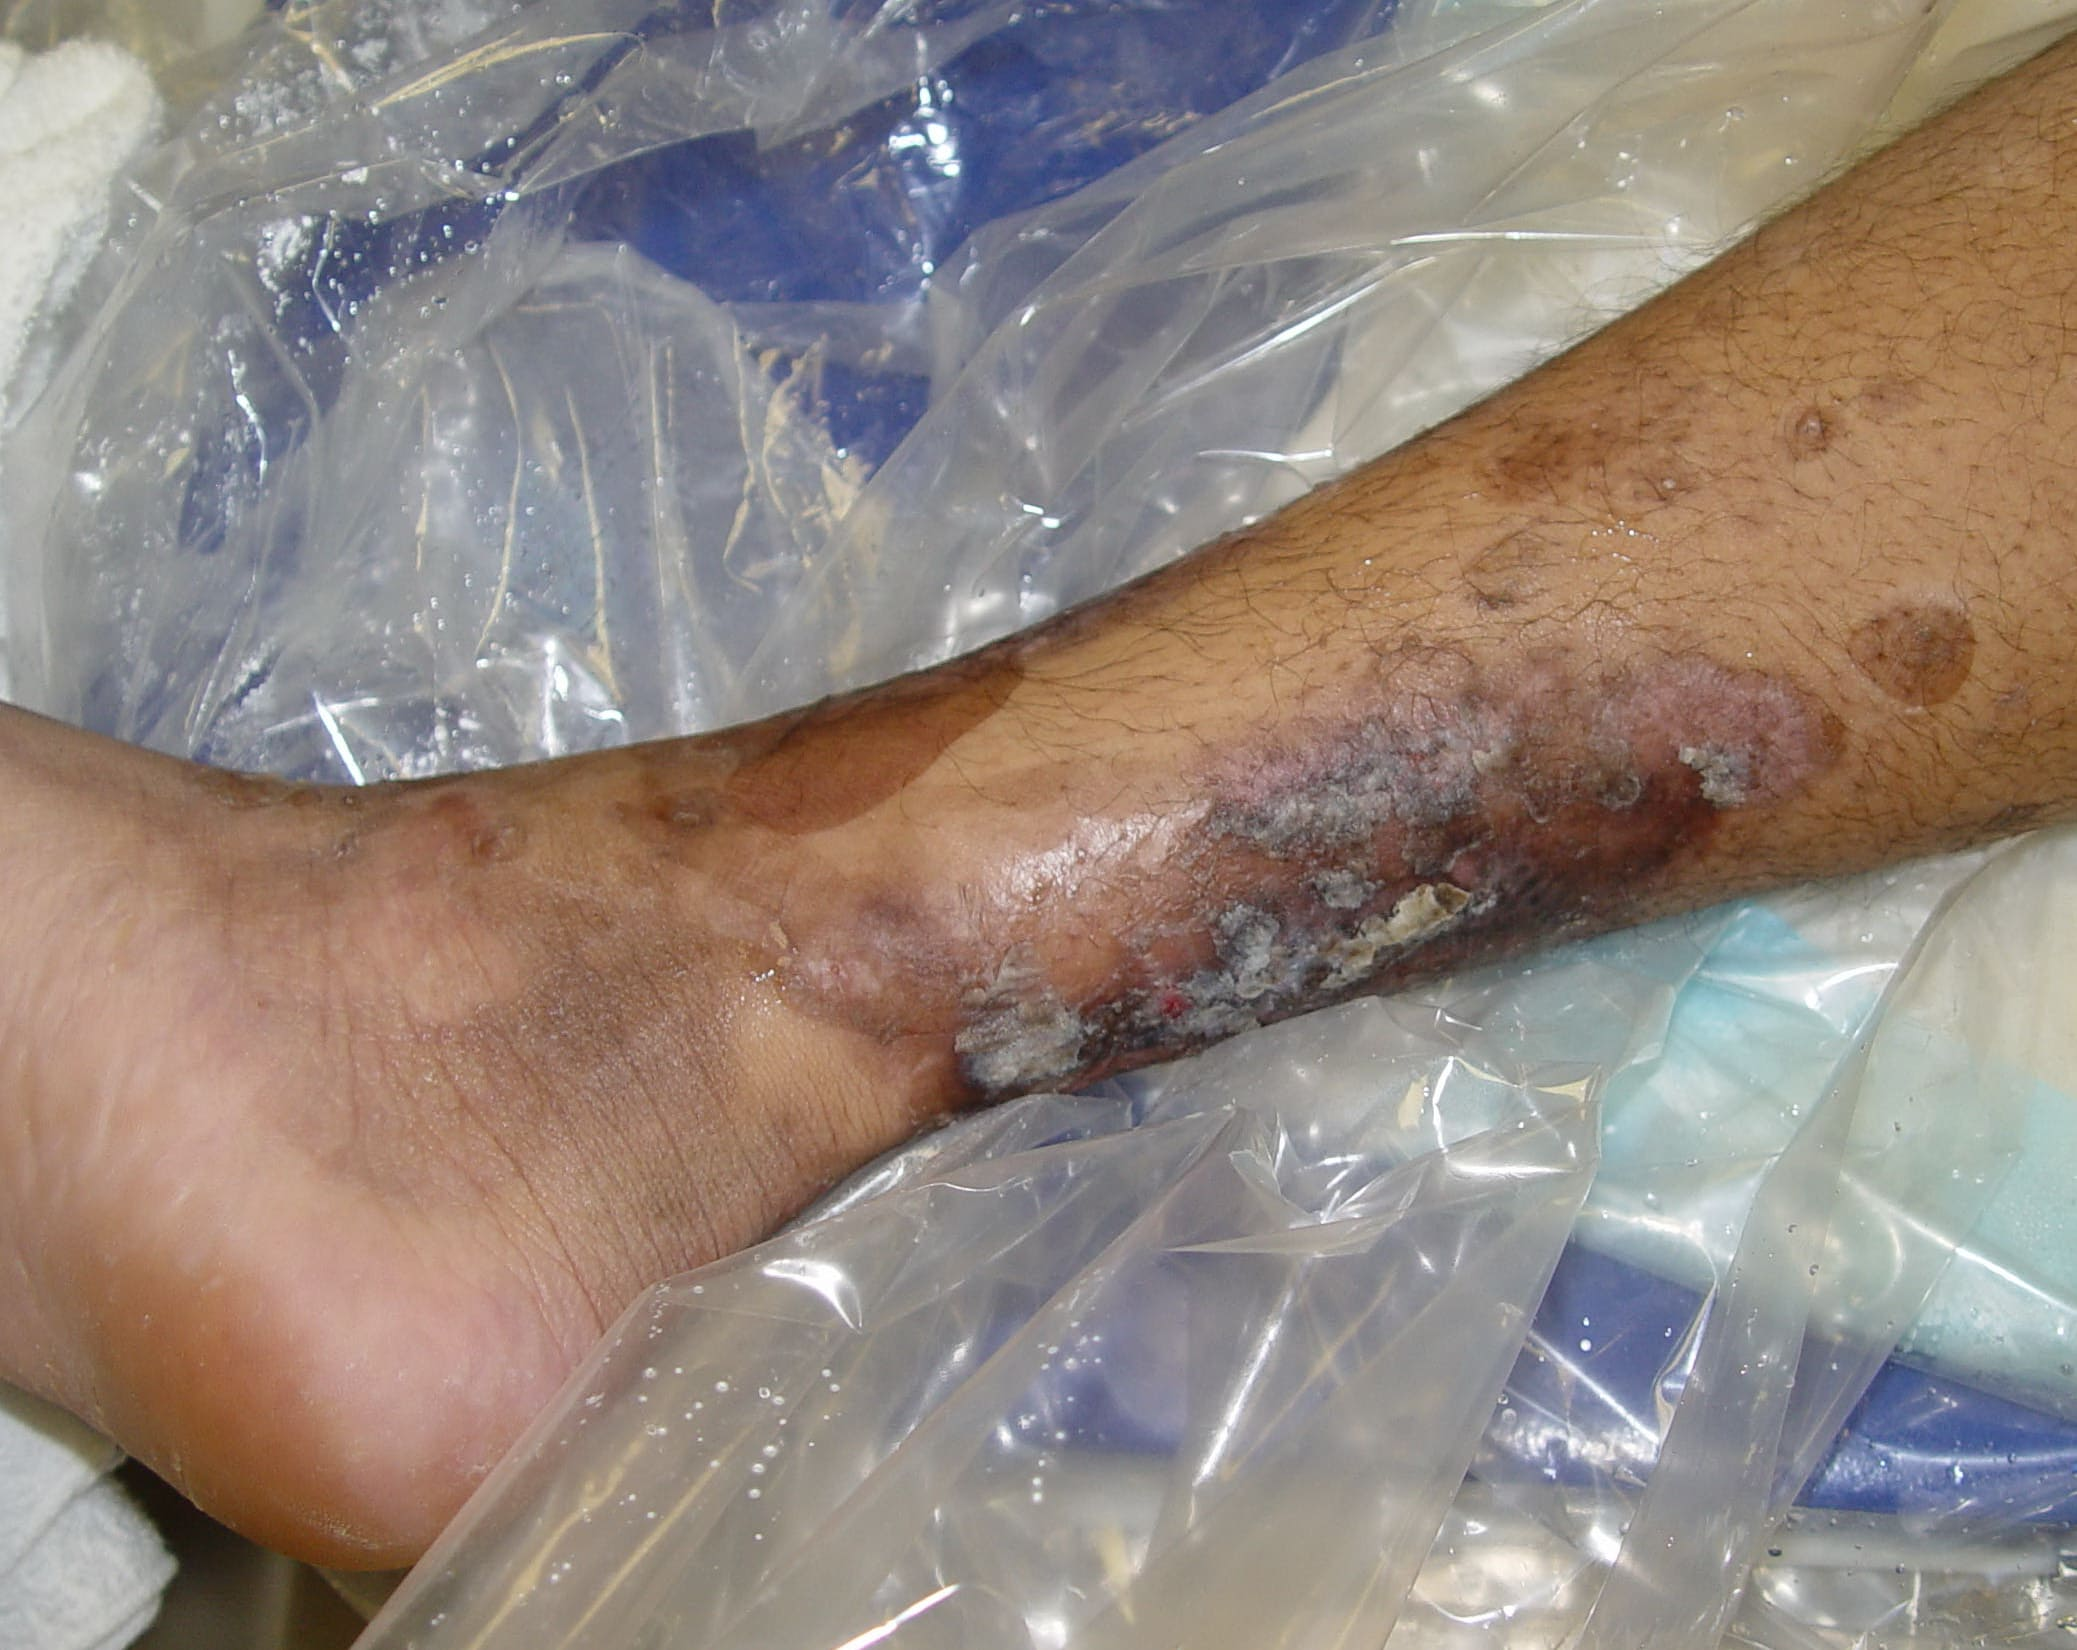

Pemphigis Vulgaris =الفقاع الشائع